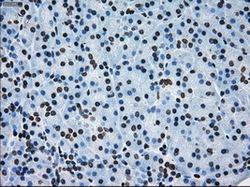

- Immunohistochemical staining of paraffin-embedded Adenocarcinoma of colon tissue using anti-ERCC1 mouse monoclonal antibody. (Dilution 1:50).